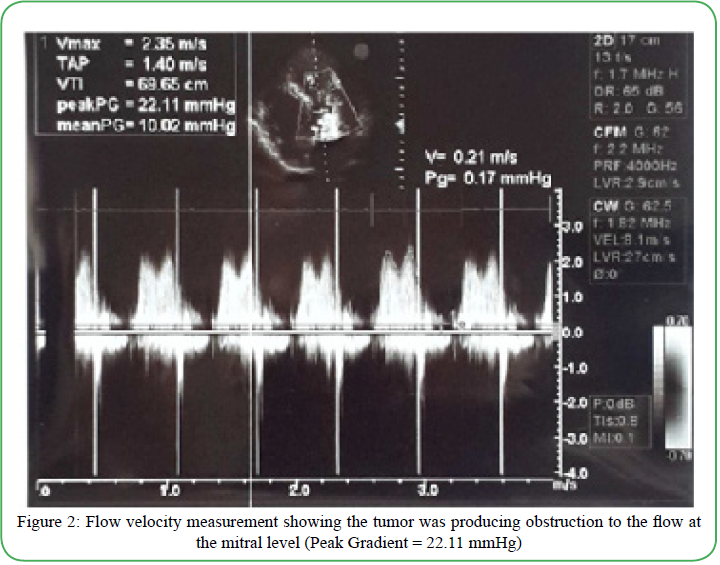

Postoperatively, whole body scintigraphy was performed, which did not detect any evidence of active osteoblastic bony metastasis. Additionally, spiral abdominal and pelvic CT scan with contrast found no abnormalities in the liver, gallbladder, spleen, pancreas,urinary bladder, or kidneys. Spiral thoracic CT scan with contrast found no evidence of mediastinal lymphadenopathy or pleural effusion. It also reported the thoracic aorta, pulmonary artery, and veins to be unremarkable. Moreover, positron emission tomography/x computed tomography (CT) scan using F-18 Fluorodeoxyglucose (FDG) found no abnormal reuptake in head and neck, lung fields, mediastinum, axillary regions, chest wall, breasts, liver, spleen, adrenal glands, pancreas, pelvis, and musculoskeletal system. Chest X-Ray, ultrasound (abdomen, retroperitoneum and pelvic), complete blood count, comprehensive metabolic panel and urinalysis were unremarkable. Post-operative echocardiogram did not find any residual mass (Figure 3).

Figure 3: Post-operative echocardiogram showing no residual neoplasm.